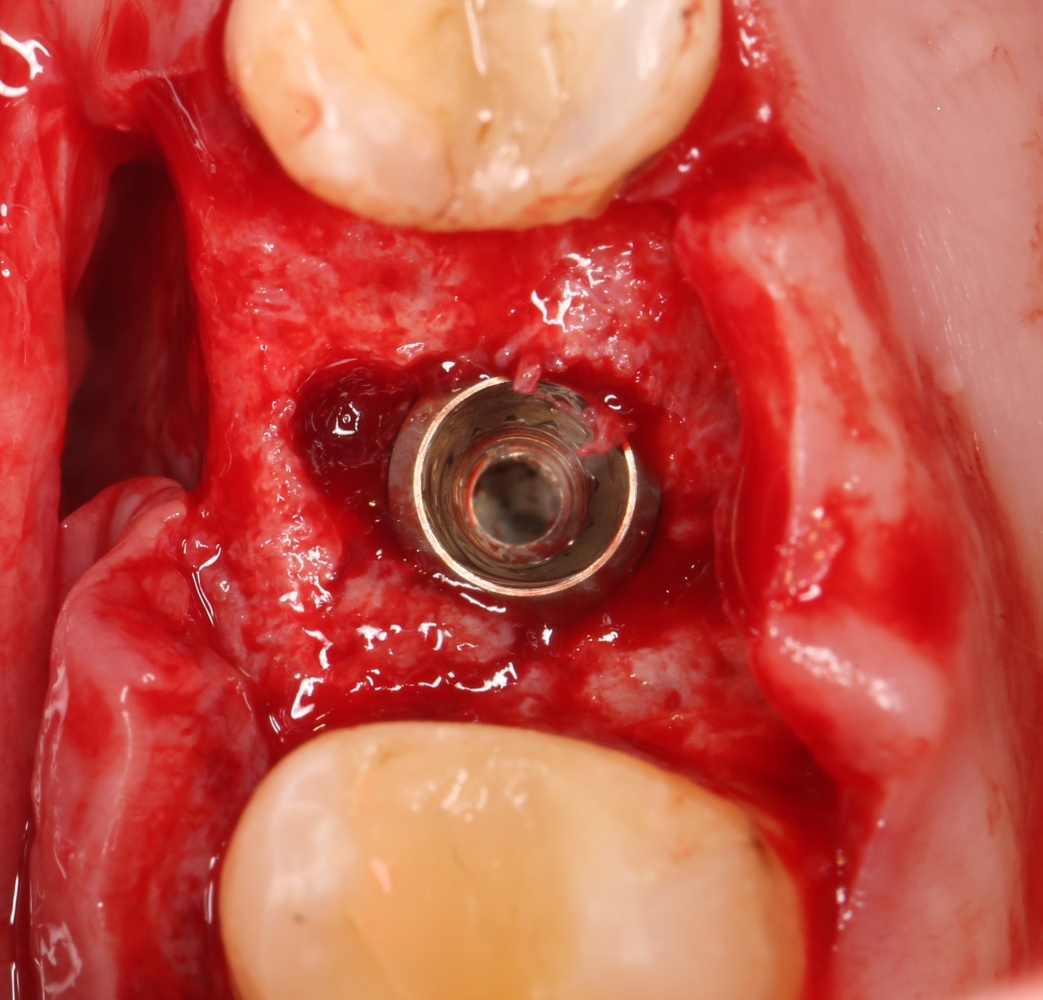

Установка имплантатов.

Напомню, что для этой работы я выбрал субкрестальные имплантаты Ankylos C/X. Они прекрасно сочетаются с любым методом остеопластики.

Я не планирую установку супраструктур или коронок, поэтому на уровень первичной стабильности можно положить болт. Даже наоборот — чем меньше крутящий момент при установке, тем лучше. Для имплантатов Ankylos и подобных им, это особенно важно. В общем, момент силы при установке — не более 10-15 Нсм.

Ремарка: имплантаты с предустановленными имплантодержателями хороши тем, что с ними легко контролировать позиционирование имплантатов. В случае с Ankylos С/Х - еще и крутящий момент. Имплантодержатель должен отсоединяться от имплантата с легким щелчком. Если его клинит, и тебе приходится прикладывать для этого усилия, то ты, однозначно, превысил момент силы во время установки имплантата. Следовательно, жди проблем.

Глянем на то, что получилось: